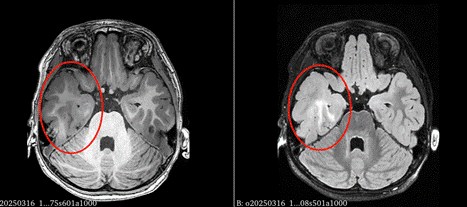

3T薄层(层厚<1mm)扫描的头颅MRI联合特殊序列(如FLAIR、SWI、QSM)可识别微小病变。例如,FCD II型在MRI上可能表现为“皮质增厚-白质信号异常-灰白质分界模糊”三联征。

图中红色圆圈内显示右侧前颞FCD病变